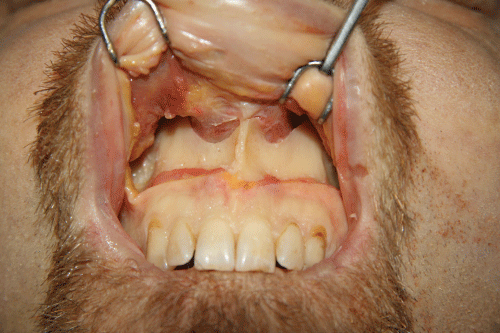

One fresh, cadaveric head was obtained through the Maryland State Anatomy Board (Baltimore, Maryland). A sublabial mucosal incision was made from tooth #6 to #11 (#13-23, FDI notation). The maxillary periosteum was elevated, exposing the lower half of the piriform aperture. Elevation of the periosteum inside the piriform aperture was also done to reveal the exact location of the bony inferior turbinate origin. A titanium plate (Synthes) was bent to resemble the Greek letter omega and affixed to the margin of the piriform aperture adjacent to the inferior turbinate face to increase projection of the piriform margin and enhance soft tissue support. Because the margin flares obliquely to the facial plane, the vector of projection is superior and lateral. Anterior rhinoscopy was used to assess any intranasal change and photographs of the technique were taken to document the procedure (Figure 1 and Figure 2).

.

Figure 2: View of the left piriform margin in the cadaver. Dotted line marks the location of the inferior turbinate attachment.